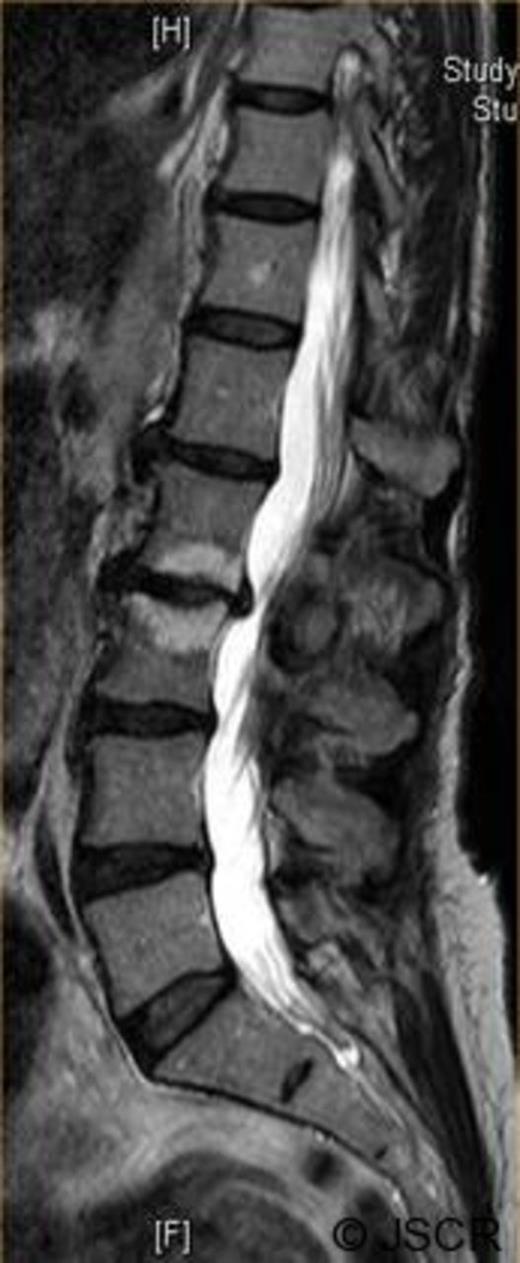

Magnetic Resonance Imaging scan (Fig. 1–4) showed L2/3 disc prolapse impinging on the right exit canal and causing L2 and L3 compression, thus she was listed for L2/3 lumbar discectomy and decompression. Examination of the right L2/L3 dermatomes revealed severe paresthesia and mild grade 4/5 weakness; reflexes were all normal. All other neurological examination was normal.

Preoperative sagittal T2 weighted image showing disc bulge at L2/3